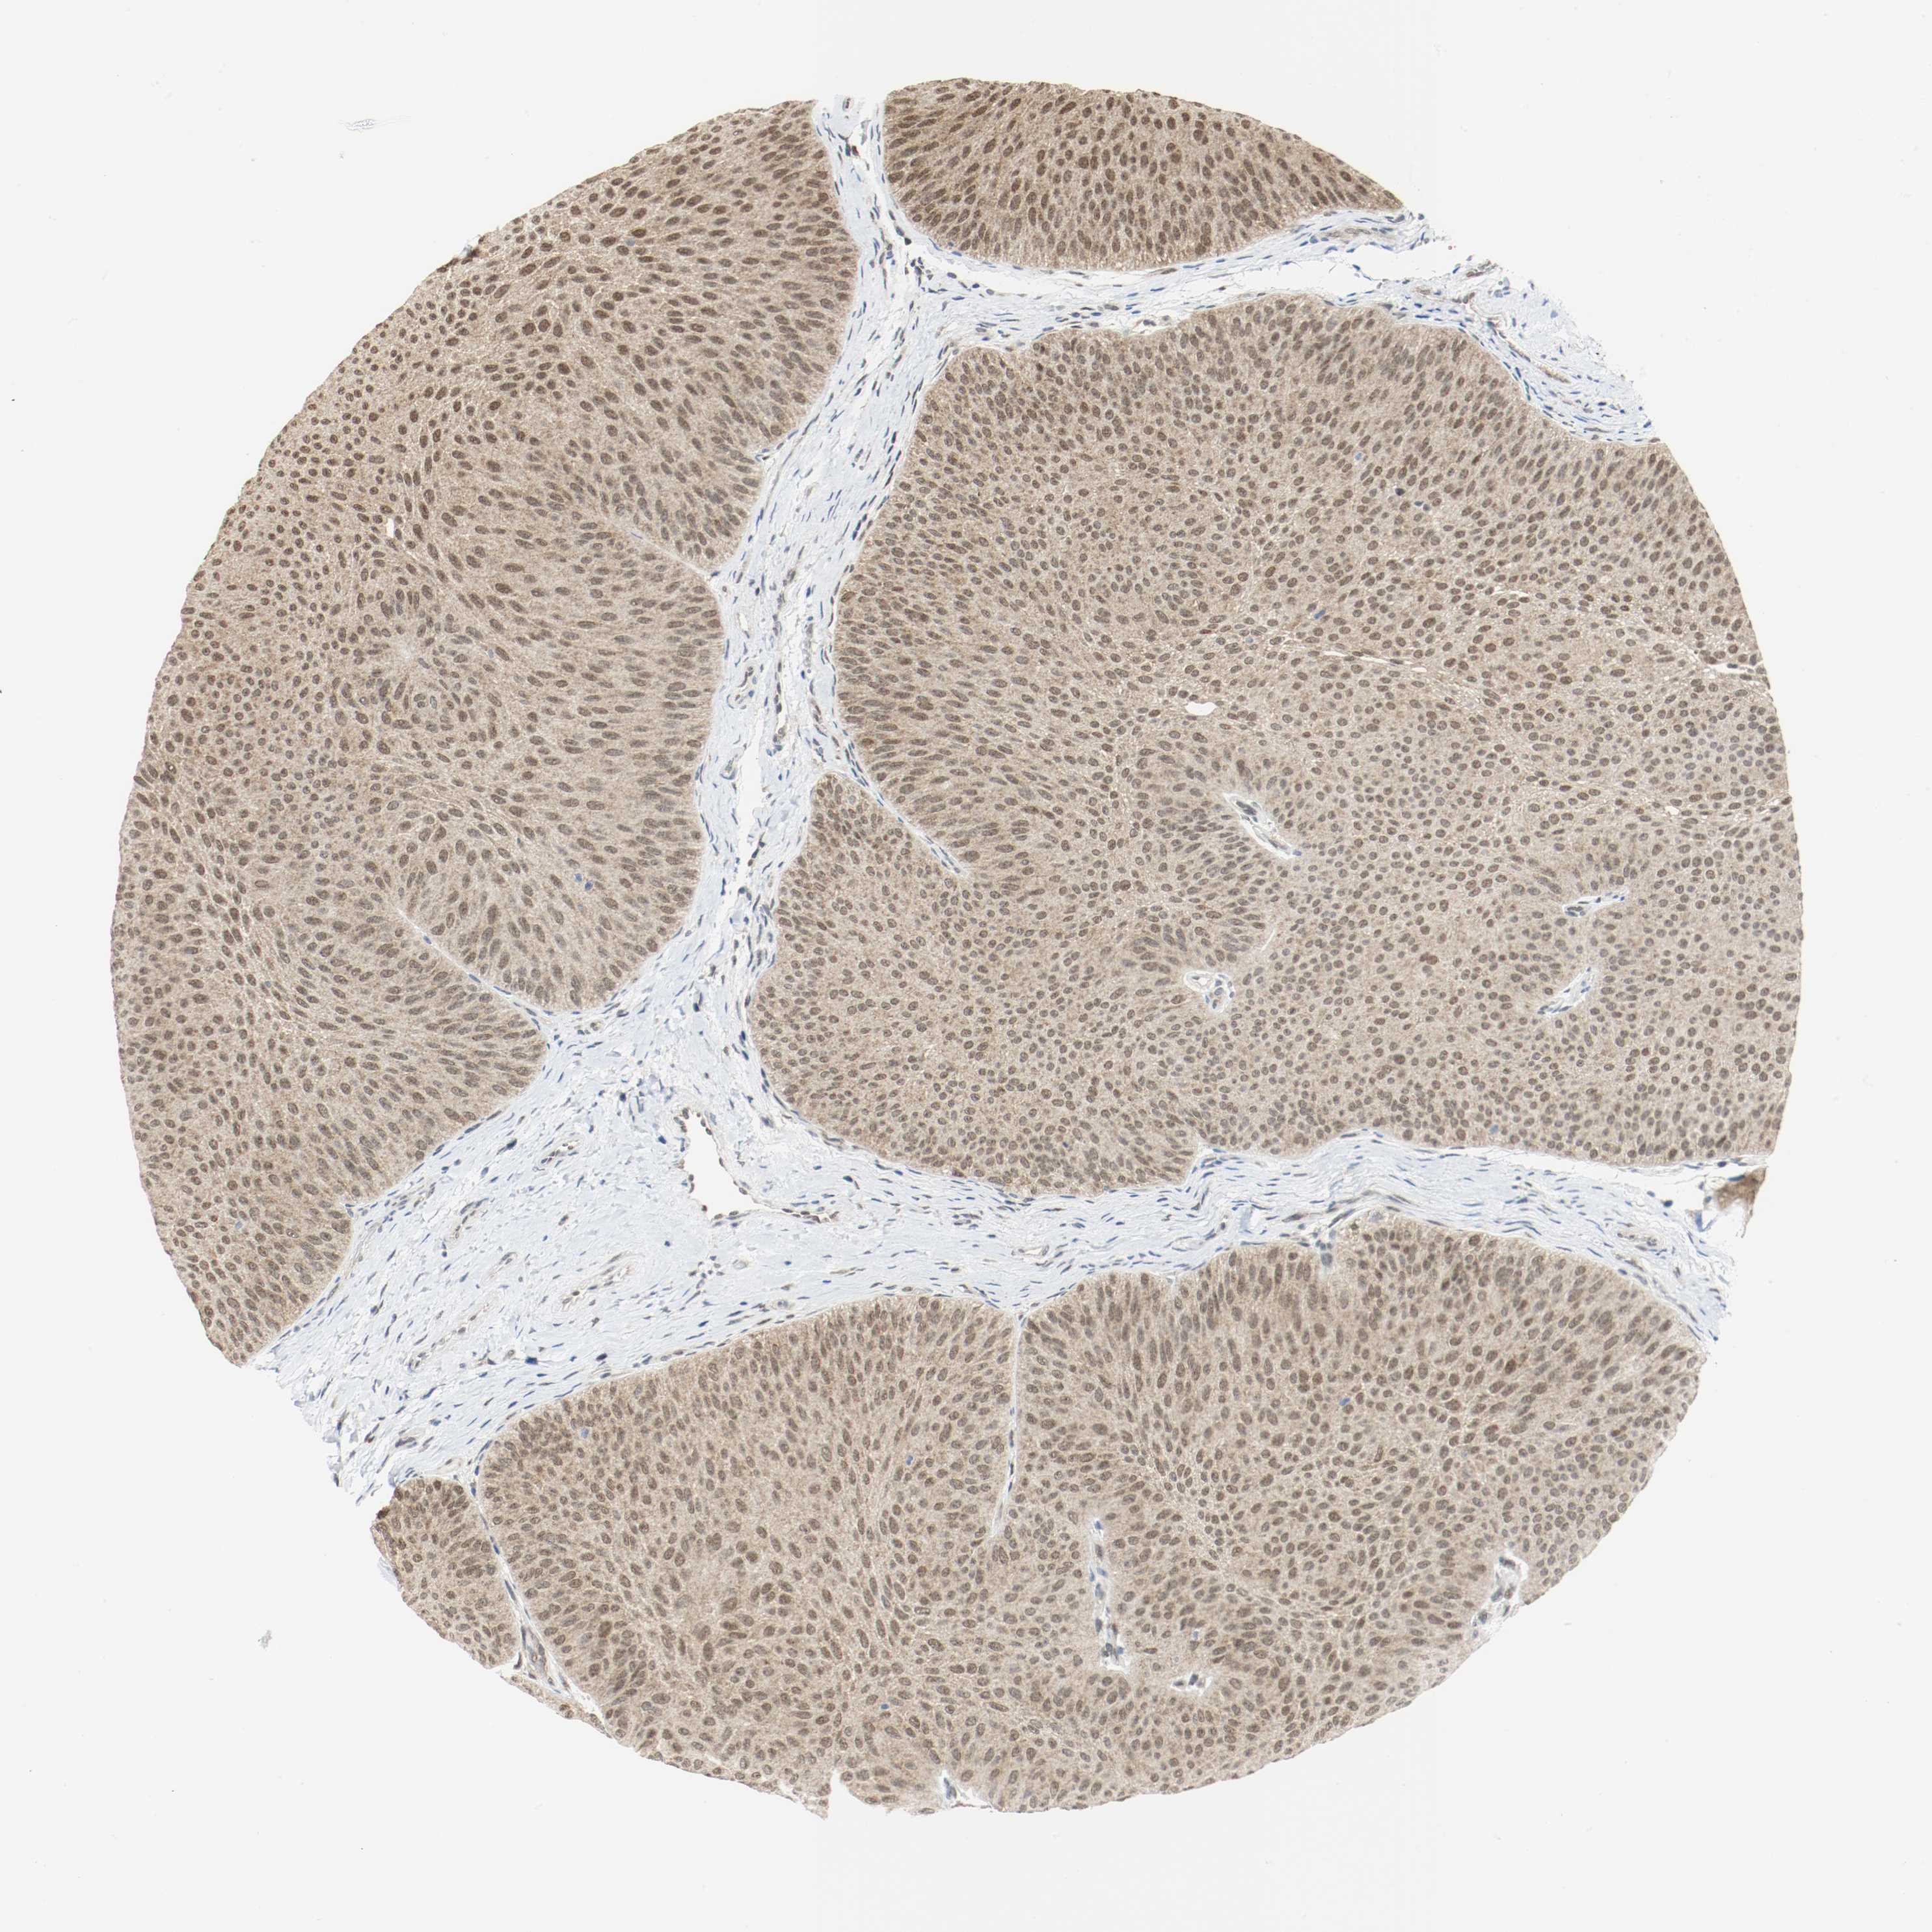

UROTHELIAL CANCER - Protein expressioni

A mouse-over function shows sample information and annotation data. Click on an image to view it in a full screen mode. Samples can be filtered based on level of antibody staining by selecting one or several of the following categories: high, medium, low and not detected. The assay and annotation is described here.

Note that samples used for immunohistochemistry by the Human Protein Atlas do not correspond to samples in the TCGA dataset.

Antibody stainingi

Antibody staining in the annotated cell types in the current human tissue is reported as not detected, low, medium, or high, based on conventional immunohistochemistry profiling in selected tissues. This score is based on the combination of the staining intensity and fraction of stained cells.

Each image is clickable and will lead to virtual microscopy that enables deeper exploration of all samples and also displays staining intensity scores, fraction scores and subcellular localization as well as patient and tissue information for each sample.

Antibody HPA043900

Antibody CAB004541

Location

Nuclear

Cytoplasmic/membranous

Cytoplasmic/membranous,nuclear

Urothelial carcinoma, High grade

Urothelial carcinoma, Low grade